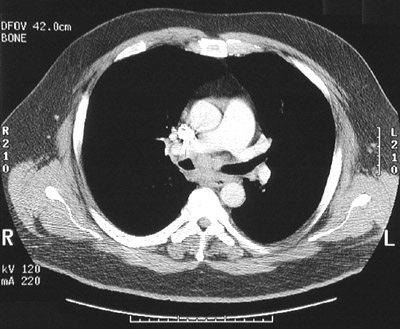

![]() | In the chest CT scan views in "bone window" above and below in the subcarinal region between the right main bronchus and the left main bronchus is a mass composed of enlarged lymph nodes. Biopsy of the mass revealed involvment by the nodular sclerosis type of Hodgkin's disease. Hodgkin's disease may involve a single group of nodes, more than one group of nodes, or may involve extranodal sites such as liver, spleen, or bone marrow. |